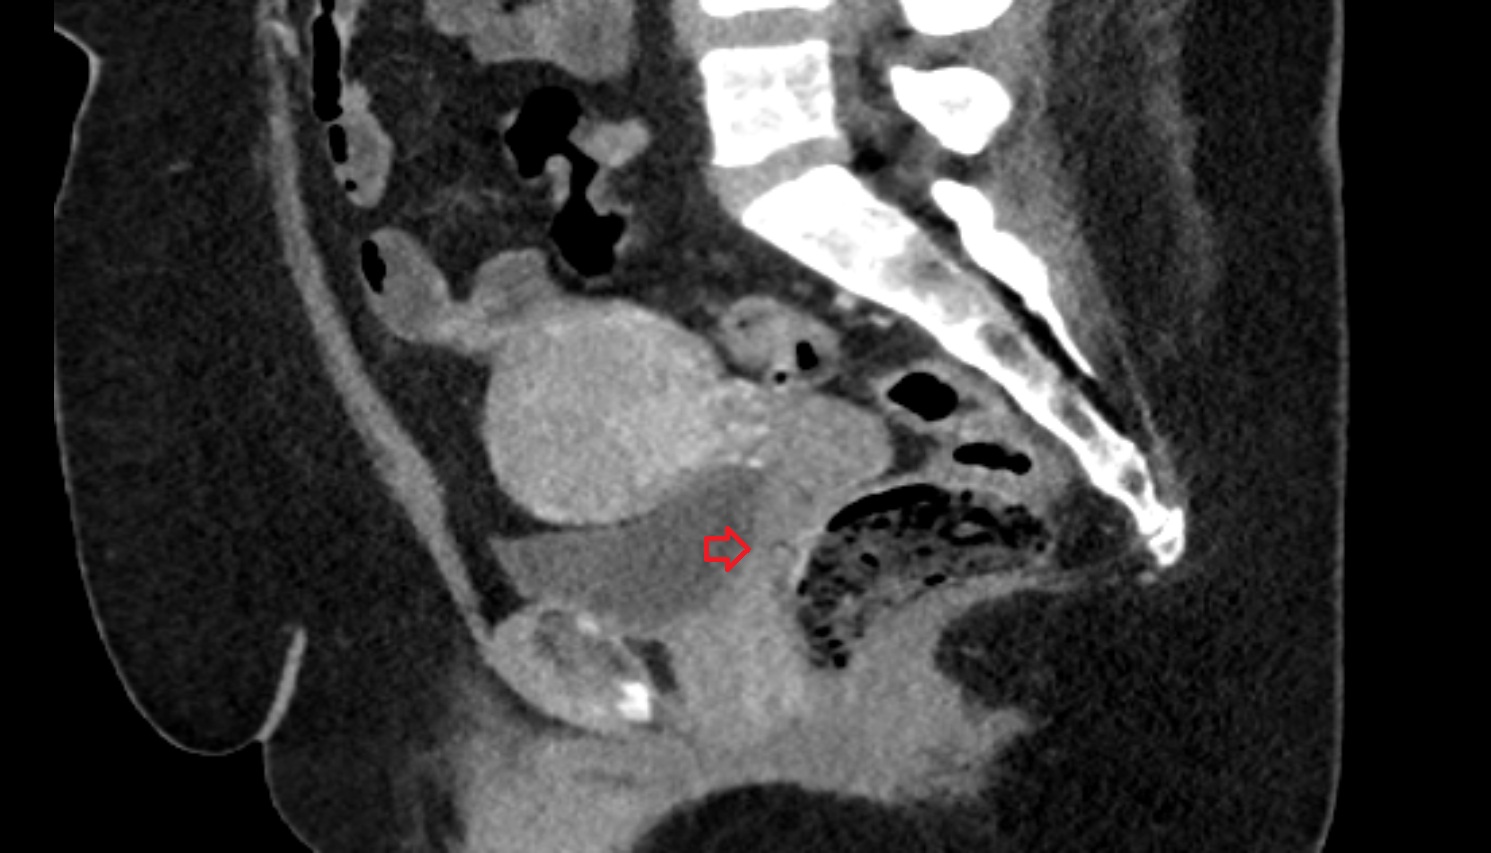

- Peripheral zone of prostate

- Anterior Fibromuscular Stroma of prostate

- Central zone of prostate

- Transitional zone of prostate